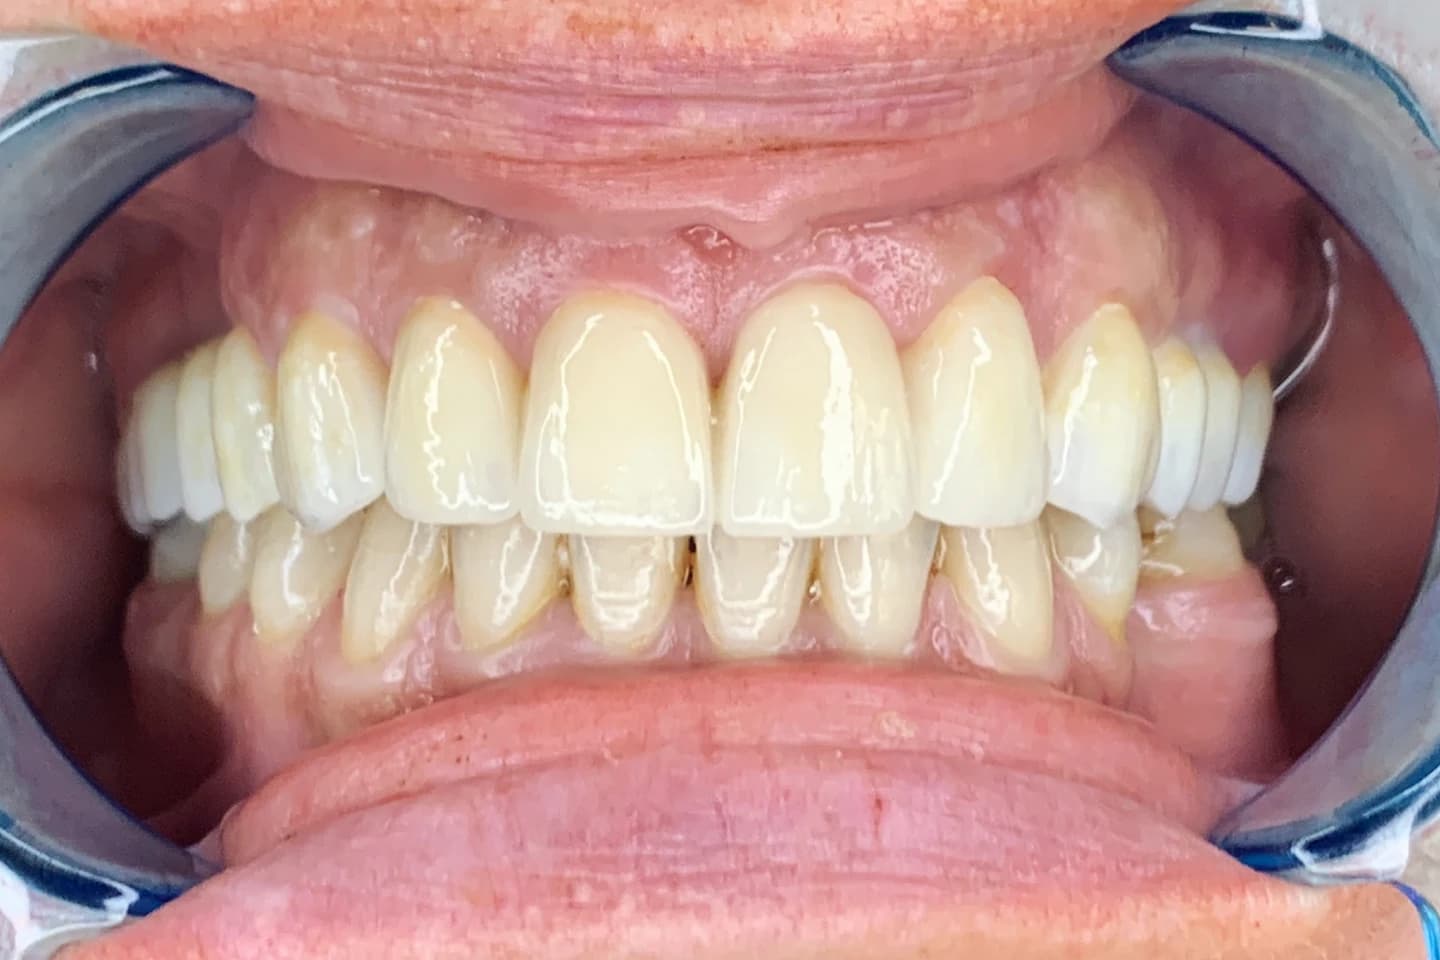

Krunice za zube - pre i posle

- Pogledajte kako krunice mogu da zaštite i obnove oštećenost kada su u pitanju zubi, vraćajući im estetiku i funkciju. Galerija radova će vas inspirisati da i vi transformišete svoj osmeh.